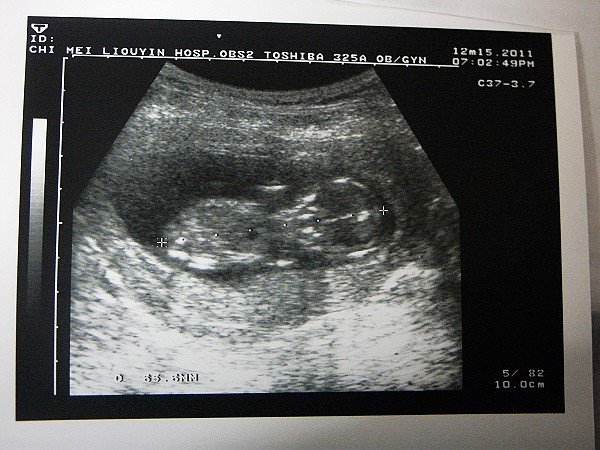

100.11.27「11w+4」

醫生照了一下魏啊啊的狀況

很好很好~阿木雖然又咳又流鼻水的

魏啊啊在肚子裡已經開始又踢又吃手指頭了

看到變成人形的魏啊啊

之前許許多多的不安似乎更加放下心了

2011.12.15 (14W+1)

小氣鬼不給看就是不給看

只有看到咖噌配!!!

檢查一切正常